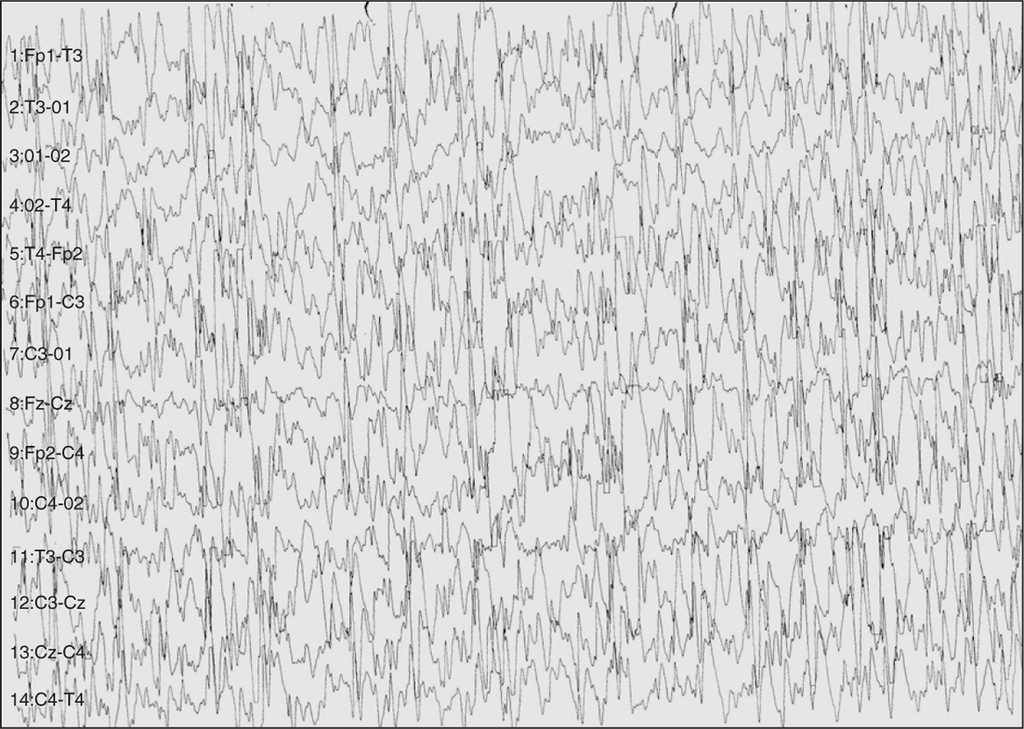

El paciente fue derivado a nuestra unidad por convulsiones intratables. En el EEG de vigilia se apreciaba un doble foco centrotemporal (rolándico) (fig. 1), que tendía a difundir y agruparse en salvas seudorrítmicas (fig. 2). En el EEG de sueño se manifestaba una gran difusión de las puntas que durante las fases de sueño lento ocupaba aproximadamente el 50 % de este (fig. 3).

Figura 1. Aspecto del trazado EEG en vigilia en el que se observan paroxismos rolándicos (frontotemporales) pero asincrónicos en ambos hemisferios. La actividad de fondo es normal.